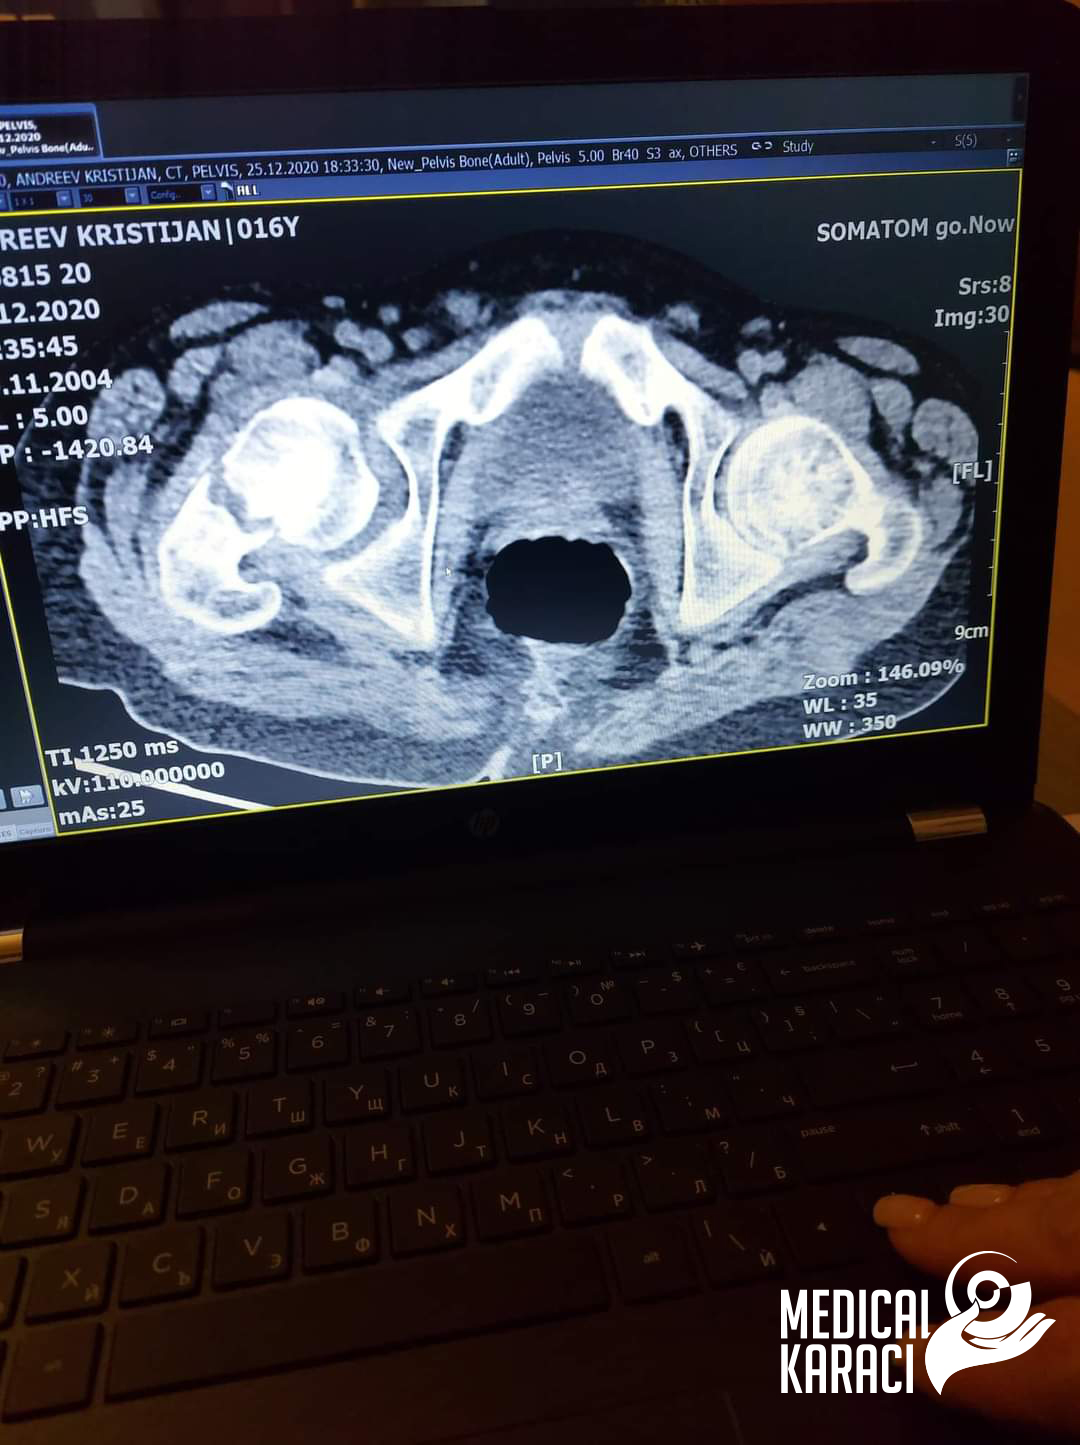

Kristijan is a child of 17 years of age who suffers from a very severe form of autism and epilepsy, in December 2020 he fell and was shot. Koga site in Macedonia kazuvaa ni deka nemoze da ho operiraat i deka nema nikogash veke da zastane na noge i da odi jas ne se otkazav, no nitu ti mila moja Zvezdelina Kara i Karaci Tours Medical denonokno istrazuvashe, him barashe i him najdobroto za Kristijan !! Kristijan blagodarenie na te te i na Prof. Dr. Mustafa Kürklü ZASTANA NA NOZE I ODI 🙏🙏Neznam kako da ti se zablagodaram za se shto napravi i pravish za Kristijan, za celata organizacija vo bolnicata Memorial Bahcelievler Hospital for the whole time that you are with us. That's why you rejoice and fight together with us🙏